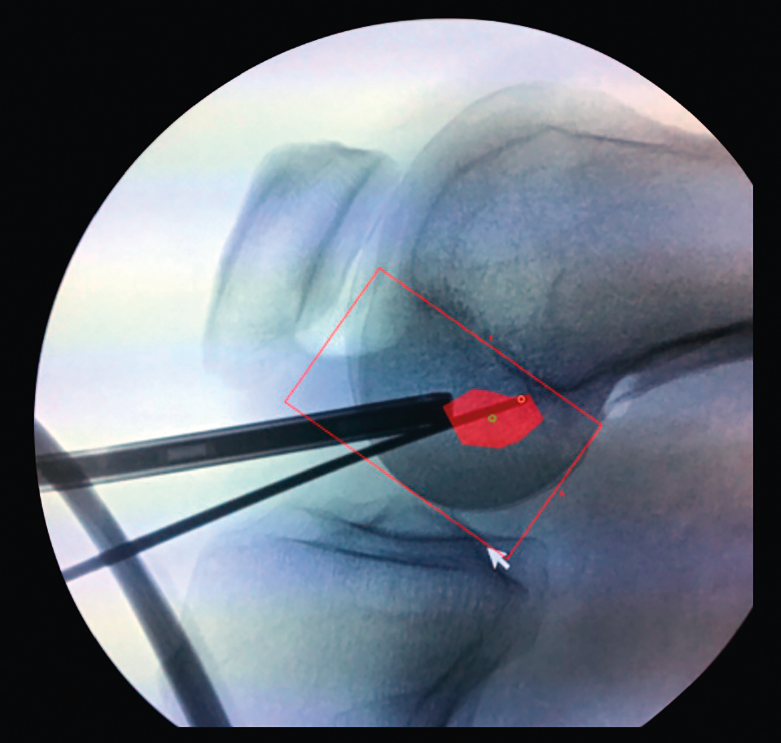

Figura 1. Laxitud en el cajón anterior. Radiología forzada.

Desde el punto de vista clínico, se consideran motivo de revisión quirúrgica aquellos casos en los que exista un desplazamiento anterior comparado con el contralateral mayor de 5 mm, pivot shift de alto grado, dolor, inflamación, sensación subjetiva de inestabilidad y limitación funcional para las actividades de la vida diaria o deportiva(9,10). Algunos autores han rebajado esta cifra a 3 mm con respecto a la rodilla contralateral o 10 mm de desplazamiento absoluto en el plano sagital(11)(Figura 1).